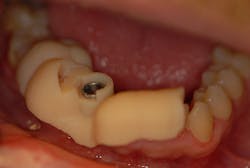

A tooth-supported fully limiting surgical guide was designed in the planning software and sent to the 3-D printer for fabrication. Once the guide was fabricated, a guide tube matching the final implant drill diameter was inserted into the guide (figure 5).